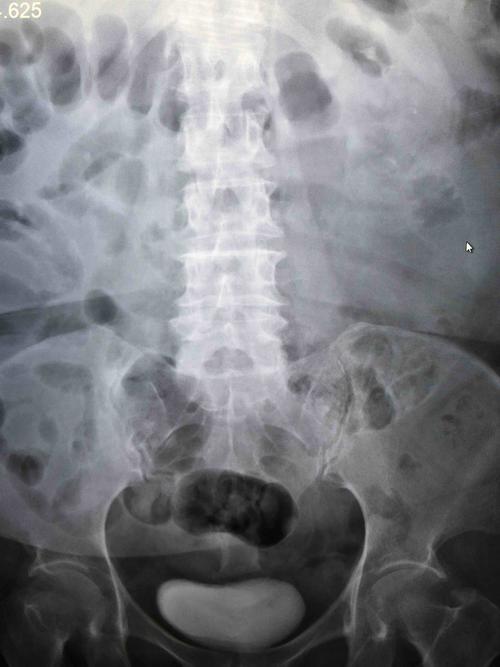

正常腹部

如何看腹部平片

正常腹部平片影像表现

腹部平片怎么看图解